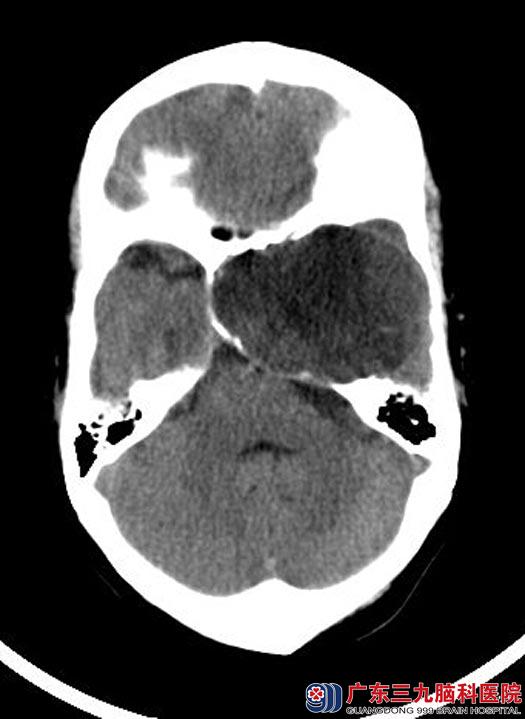

广东三九脑科医院神经外五科鲁明主任建议行头颅CTA检查进一步了解肿瘤血供情况,结果提示:左侧中颅窝示一卵圆形囊实性占位性病变,大小约69.4mm×51.9mm×63.9mm,其内可见多条小血管走行,邻近颅骨受压变薄,左侧颈内动脉受压变形并向右移位,左侧大脑中动脉受压向上、向前移位。

手术前